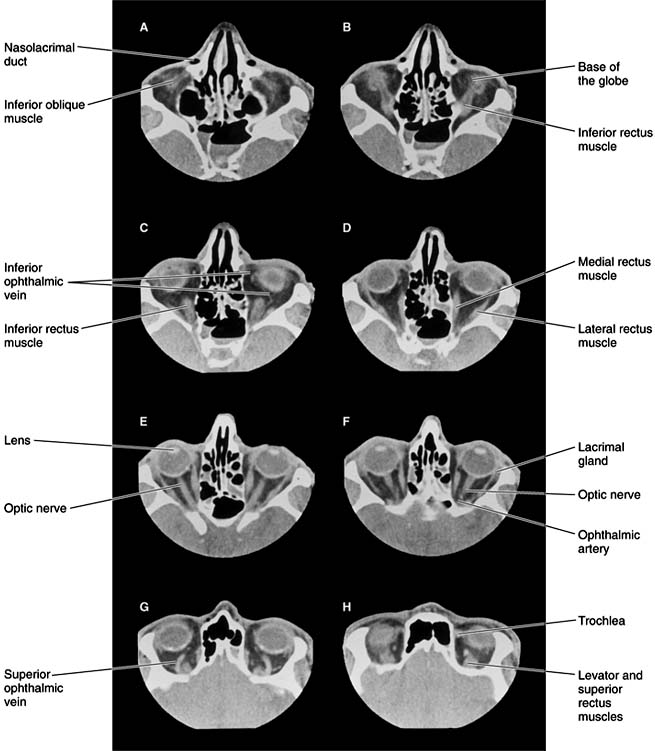

Chapter 13: Orbit Author: Orbit PHYSIOLOGY OF SYMPTOMS Owing to the rigid bony structure of the orbit, with only an anterior opening for expansion (Chapter 1), any increase in the orbital contents taking place to the side of or behind the eyeball will displace that organ forward (proptosis). Protrusion of the eyeball is the hallmark of orbital disease. Expansive lesions may be benign or malignant and may arise from bone, muscle, nerve, blood vessels, or connective tissue. A mass may be inflammatory, neoplastic, cystic, or vascular. Protrusion is not in itself injurious unless the lids are unable to cover the cornea. The underlying cause, however, is usually serious and sometimes life-threatening. Pseudoproptosis is apparent prop-tosis in the absence of orbital disease. Such confusion may arise with high myopia, buphthalmos, and lid retraction. History and examination provide many clues to the cause of proptosis. The position of the eye is determined by the location of the mass. Expansion within the muscle cone displaces the eye straight ahead (axial proptosis), whereas a mass arising outside the muscle cone will also cause sideways or vertical displacement of the globe directly away from the mass (nonaxial proptosis). Bilateral involvement generally indicates systemic disease, such as Graves' disease. The term "exophthalmos" is often used when describing proptosis associated with Graves' disease. Pulsating proptosis reflects the pulse of an orbital vascular malformation or transmission of cerebral pulsations in the absence of the superior orbital roof, as in neurofibromatosis-1. Positional proptosis-which changes with Valsalva's maneuver-is a sign of orbital varices or meningocele. Intermittent proptosis may be the result of a sinus mucocele. The Hertel exophthalmometer (see Chapter 2) is the standard method of quantifying the magnitude of proptosis. Serial measurements are most accurate if performed by the same individual with the same instrument. With the change in position of the eyeball, especially if it takes place rapidly, there may be enough mechanical interference with the movement of the eye to cause dissociation of ocular movements and diplopia (double vision). Pain may occur as a result of rapid expansion, inflammation, or infiltration of sensory nerves. Vision is not usually affected early unless the lesion arises from the optic nerve. Pupillary signs and color vision testing may identify subtle optic nerve compression or involvement before acuity is reduced significantly. Involvement of the superior orbital fissure by trauma or tumor produces a characteristic combination of diplopia resulting from disturbance of function of the oculomotor, trochlear, and abducens nerves and corneal and facial anesthesia (ophthalmic division of trigeminal nerve), known as the orbital fissure syndrome. Expanding lesions at the orbital apex result in the orbital apex syndrome, characterized by proptosis and optic nerve compression, variably accompanied by the diplopia and corneal and facial anesthesia seen in the orbital fissure syndrome. DIAGNOSTIC STUDIES 1. IMAGING Imaging by computed tomography (CT scan) (Figures 13-1 and 13-2) was a major advance in orbital diagnosis. Continued improvement in resolution quality-as well as three-dimensional reconstructions-have made CT the single most important diagnostic study in the investigation of orbital disease. Contrast enhancement with CT during study of vascular lesions sometimes provides additional information. Magnetic resonance imaging (MRI) is capable of displaying subtle changes within soft tissue that cannot be imaged with CT, but it is less useful for bony changes. A surface coil applied directly to the orbit enhances image resolution. MRI is contraindicated in the presence of a ferrous intraorbital or intracranial foreign body. Ultrasonography The use of ultrasonography in the diagnosis of orbital disease has largely been supplanted by CT and MRI. Although it is a noninvasive and inexpensive form of imaging, its usefulness in both A and B mode is limited to the anterior portion of the orbit. It is of greatest value in the hands of the clinician- ultrasonographer capable of interpreting "real time" images. Venography Venography is occasionally useful in defining the extent of orbital venous disease. Although the diagnosis can be made by MRI, contrast injection into the orbital veins via a scalp vein can sometimes reveal the presence of varices that have escaped detection by CT. Angiography Selective carotid angiography with bone subtraction is sometimes necessary to make the diagnosis of certain orbital vascular disorders. In spontaneous, low-flow dural carotid artery-cavernous sinus fistula, angiography is required for delineation of the extent of involvement and for treatment by embolization. Radiography Plain x-rays are sufficient for diagnosis of many orbital disorders such as fractures. However, the thin walls of the orbit are difficult to visualize even with tomography, and CT or MRI imaging is used to determine the extent of injury. Dacryocystography and radionuclide scanning can sometimes be helpful in localizing the site of lacrimal obstructions, but these procedures are seldom used. The results are difficult to interpret, and treatment is seldom altered by the findings. Positive contrast radiography and pneumo-orbitography are no longer used. Orbital thermography is a research procedure. Fine-Needle Aspiration Fine-needle aspiration is an invasive procedure that has proved very useful in orbital diagnosis. Cytology specimens can be aspirated from a lesion the exact location of which is determined by CT imaging. Cytopathology can be inconclusive but is often invaluable. Page 1 of 7 10.1036/1535-8860.ch13 |